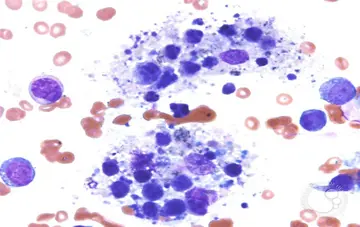

لنفوهیستیوسیتوز هموفاگوسیتیک